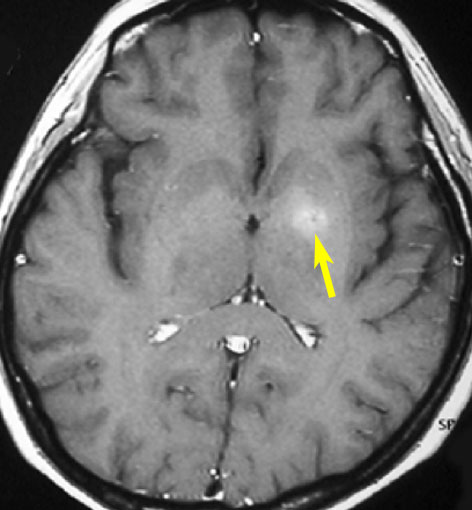

若い患者さんのリンパ腫です。左が診断時MRIで,黄色の矢印でみれる3ヶ所に同時にリンパ腫が発生しています。定位生検術後にすぐにMTX化学療法を3コースしたら,真ん中の画像になりました。ほとんど消失しているのですが,矢印の先にぼーっと少し残っているのでCR(消失)とはいいません。化学療法を終えた後に全脳照射30グレイをしたら右の画像になり治りました。これは順調な治療経過の例です。

矢印の所を定位脳手術で取りました。病理の結果がリンパ腫と確定されましたから,MTX化学療法をしてから放射線をあてたら,右側のMRIのように腫瘍は消えました。患者さんの症状は良くなって退院したのですがーー。